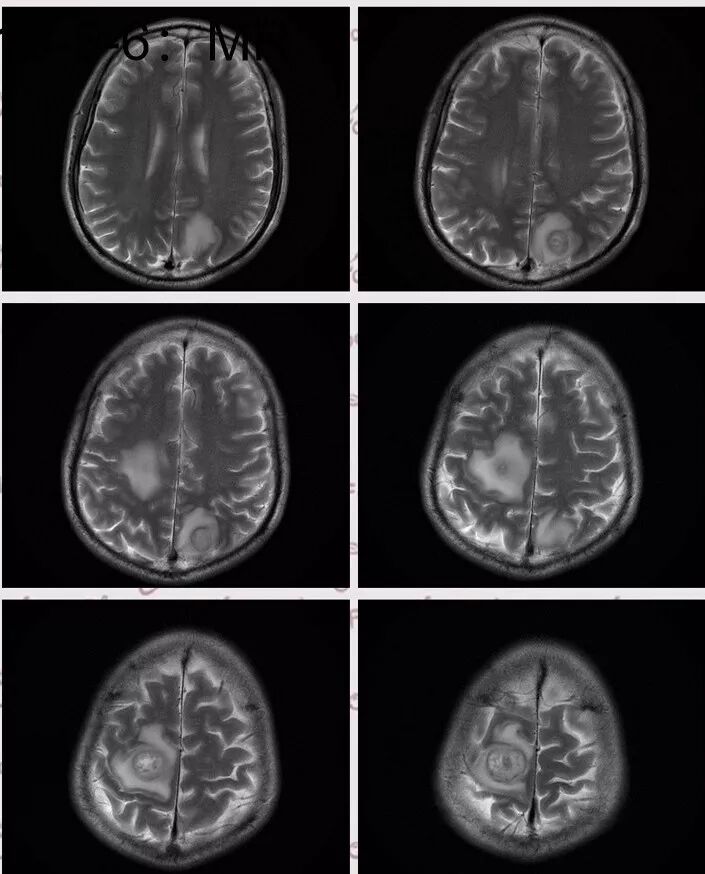

右肺下叶见不规则软组织影,边缘不清,内夹杂气体,背段支气管未见明显阻断,增强扫描下叶病灶内见类圆形低强化区,其边缘光滑,见低强化区壁,颅脑左侧枕叶及双侧顶叶见多发长T1长T2信号,T2高信号内见类圆形异常信号,壁呈低信号,DWI环形壁未弥散受限,内容物弥散受限,周围为水肿区,增强扫描呈多发环形强化,考虑血源型感染,颅内及右肺下叶脓肿形成

DWI值对鉴别脑脓肿与囊性脑转移瘤有重要意义。包膜期脑脓肿其内容物主要为炎症细胞、微生物及蛋白质,其黏稠度相对较高,水分子弥散受到限制,DWI表现为均匀高信号。转移瘤囊变区主要以浆液性坏死物为主,其黏稠度相对较低,水分子扩散速度相对较快,DWI表现为低信号

脑脓肿和囊性脑转移瘤的鉴别点就是粘液(结合水)浆液(自由水)的鉴别

下图是例举其他病例:

颅内环形的高信号,但是可以发现这个的DWI环是厚的,但是增强扫描的环是非常薄的,如果是肿瘤的,就是壁的弥散受限是肿瘤细胞的话,那么他强化的环应该跟DWI的环的厚度是一样的,所以这个环形的低DWI高信号应该是脓肿。而且就是关于这个脓腔壁的,就是脓腔的外壁是非常模糊的,而内壁还是相对光整,环不是很完整。下面一个图,没有给到,DWI上可以看到沿着破溃的脓肿壁向外侵出去的感觉,如果是环形转移的,那么它的那个内壁是更加不光整,而外壁是相对比较清楚一些的。

这个颅内病灶增强扫描的无强化区范围与DWI高信号范围是一致的,所以还是脓腔内受限,至少时期不那么典型,不是纯粹的高信号,DWI是厚层、增强是薄层;而且扫描角度也不一样,所以无法完全对上

脓肿内的坏死、脓液形成也不是一次性完全形成的,就像在肝脓肿内,信号也是不一致的。重点还是在于强化区的地方弥散受限了还是无强化区的地方受限了,还是那句话,强化壁比弥散壁薄很多,无强化区比弥散不受限区范围大多了

3.脑内多发混杂信号病灶,显著长T1、显著长T2信号为主。注意TW1及TW2均显示环形等密度影(这在转移瘤是非常罕见的)且出现相应的环形强化。中央液化区DW扩散受限以及周边广泛水肿等,都符合典型多发脑脓肿改变。

4.脓腔较大,也更符合细菌感染。(脑内结核、隐球菌及奴卡菌感染病灶通常不易有如此大范围)

综上患者符合肺脓肿及脑脓肿诊断,病原菌以肺炎克雷伯杆菌等感染可能性较大